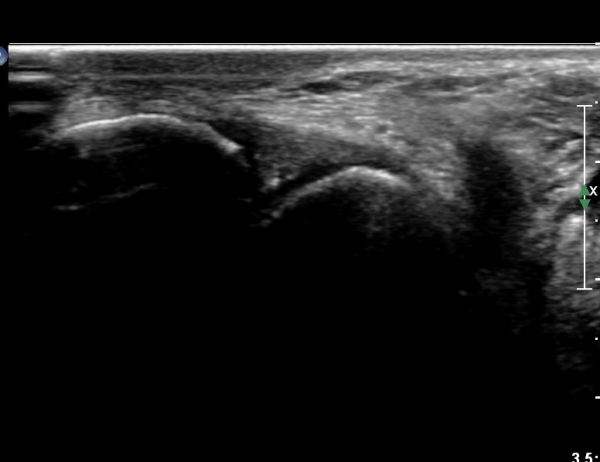

Á¾°ñ Àü¹æ µ¹±â(anterior process) °ñ±Ø°ú Ȱ¾×¸·¿° ¼Ò°ßÀ» º¸ÀÓ(»çÁø 3, 4).

Sinus tarsi Á¾´Ü¸é, Ⱦ´Ü¸é°Ë»ç¿¡¼­ sinus tarsi ³» ºÎÁ¾À» º¸ÀÓ(»çÁø 5, 6).